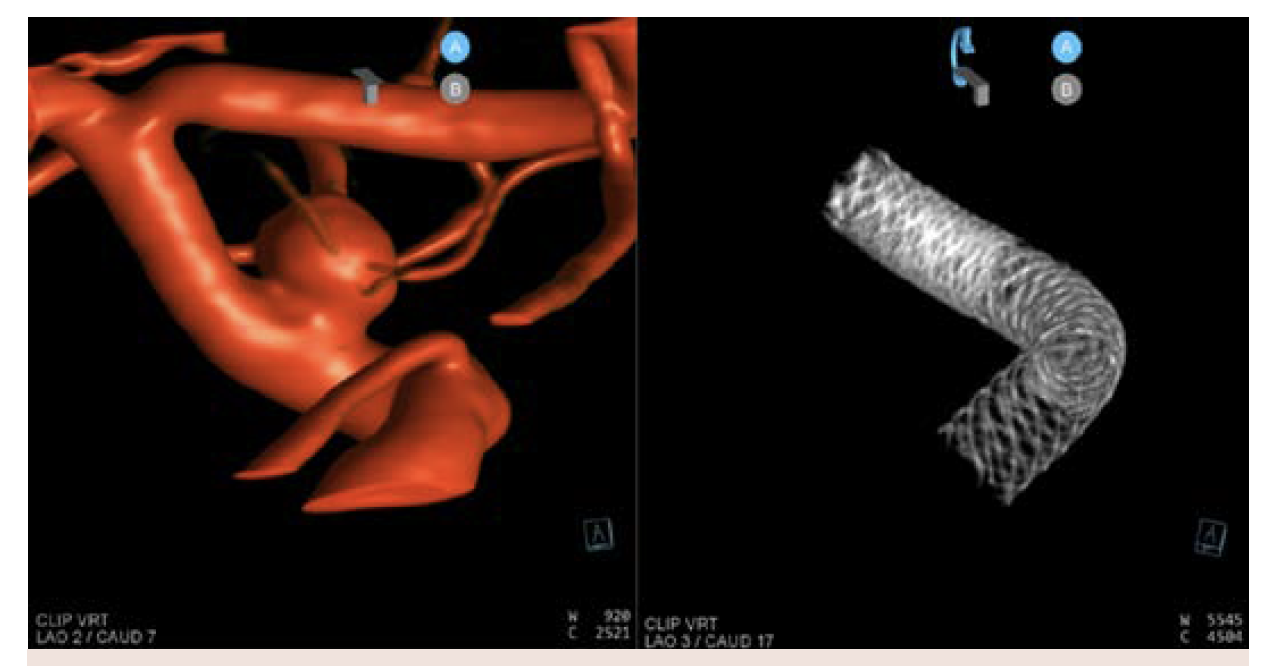

A 3D reconstruction of the aneurysm and DynaCT Micro image of the stent construct was performed (Figure 8). This is a 3-stent construct. There was extraordinary coverage over the neck of the aneurysm with 2-stent coverage over the distal ophthalmic segment and 1-stent coverage extending into the cavernous segment.